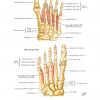

Atlas Giải Phẫu Chi Dưới (Netter) | Bài giảng CĐHA

* Tác giả: Frank H. Netter v6 – 2016